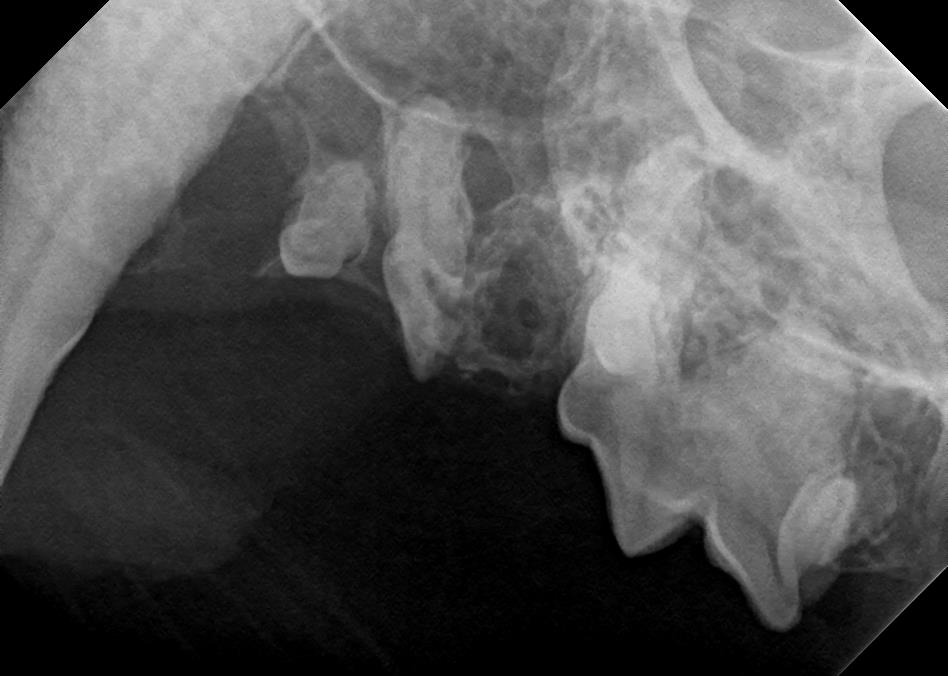

Examples of dental problems:

At A Couple of Vets, our animal hospital staff is well-versed in the latest dental cleaning techniques to remove plaque and tarter from the teeth’s surface as well as from below the gum line. We perform dental x-rays at every cleaning to ensure that the teeth are completely healthy. They may look good on the surface, but many problems occur below the gum line and are only visible with x-rays.